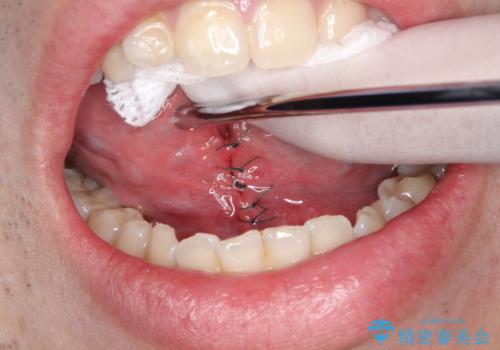

手術は局所麻酔下で行われ、舌小帯を切開し、縫合します。

手術後は、通常、数日から数週間で回復します。痛みや腫れがある場合は、医師の指示に従って適切な処置を行います。